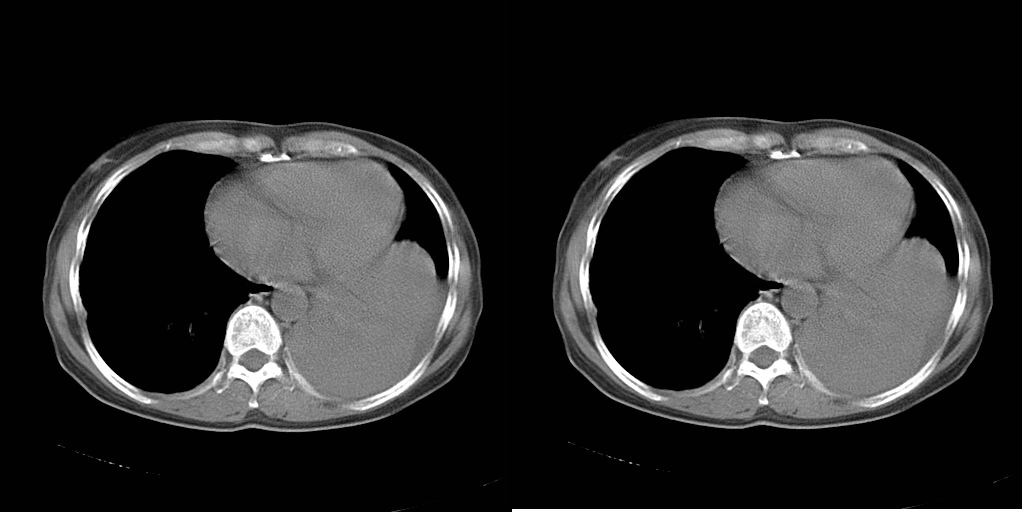

以下是引用dyqct在2007-1-23 15:01:00的发言:[br]左肺下叶实变、略萎陷,近肺门下部密度不均。上腔静脉后及隆突前见肿大淋巴结。余未见异常。[br]考虑:1、左肺下叶中心型肺癌伴肺不张、纵隔淋巴结转移;[br] 2、建议增强扫描并做任意平面重建确定肿块范围及支气管受累情况。

以下是引用同在2007-1-23 19:59:00的发言:[br]左肺下叶中央型肺癌伴肺不张及纵隔淋巴结转移.